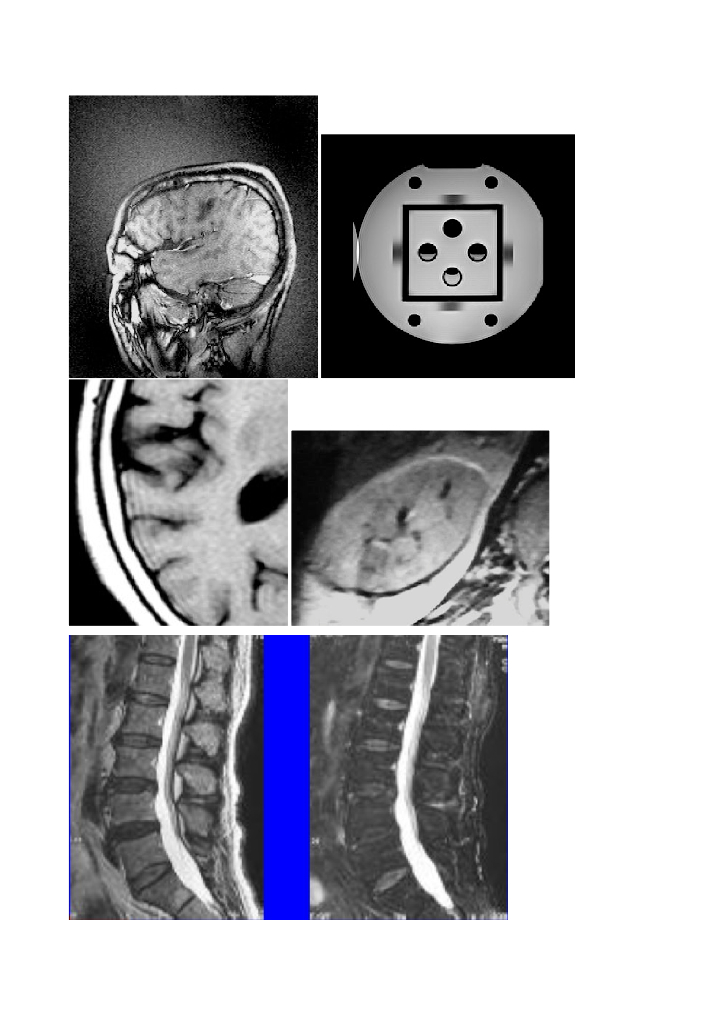

《现代医学成像技术》MRI伪影素材库.pdf